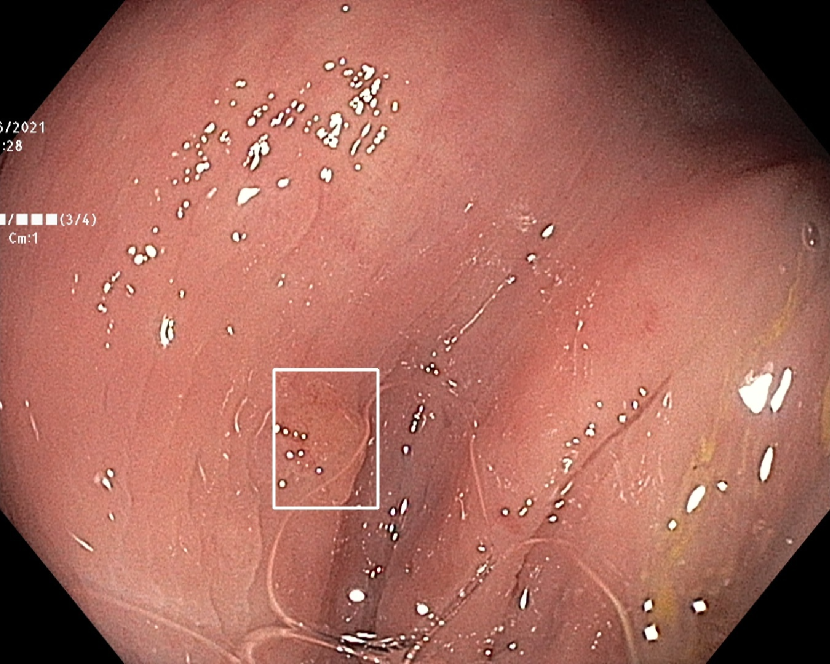

(h)

Figure 7: Sample images from the testing dataset, with results from the best performing model. White boxes are the ground truth annotations, blue ellipses are the model predictions. In the first row, examples of false negative polyps are shown: (7(a)) a small and distant polyp, (7(b)) a polyp partially covered by water/bubbles, (7(c)) a polyp framed in blue light, (7(d)) a large polyp near the image boundary and overexposed. In the second row, examples of false positive detections are shown: (7(e)) the model activates on a artifact due to stain and motion blur, (7(f)) the model activates on a solid residue, (7(g)) the model activates on an area of the colonic mucosa that is not well inflated, (7(h)) the model activates on a dark and distant area of the colonic mucosa whose shape is similar to a polyp.

Finally, in Figure 7, we display examples of false negatives and false positives from the test set, generated by the best performing model. To visually assess the performance on a whole video, we have uploaded a 60-minute colonoscopy video featuring 6 polyps, the longest in our test set, at https://figshare.com/s/fbb0834a21082984336c (with predictions marked in cyan and ground truth boxes in white). The image examples illustrate how the model struggles with small, occluded, or poorly imaged polyps, and generates false positives in areas that visually resemble polyps, often due to motion or suboptimal imaging. These observations persist throughout the entire video analysis, highlighting the importance of minimizing false positives throughout the entire procedure while maintaining high polyp recall.